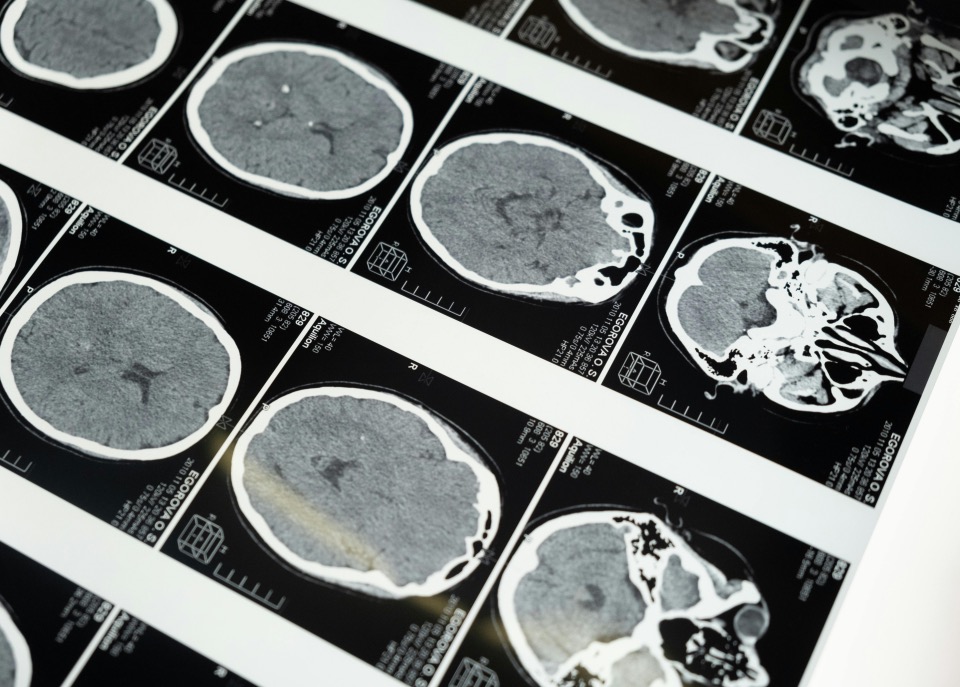

SupPACS 医学影像存储与通讯系统

SupPACS 医学影像存储与通讯系统超星智能化医疗的重要组成部分,与智能医疗信息系统SupX一体化设计,共享同一个云原生、微服务平台,支持本地化部署,也支持云端部署。支持云胶片功能,医疗机构可以采用云胶片功能取代传统纸质胶片。支持大动态影像的连续传输,可以快读打开远端图像;支持高端影像处理,支持三维重建,支持血管剥离等技术;支持报告语音输入和自动排版,可以取消现在的报告助理岗位,而由AI完全控制。